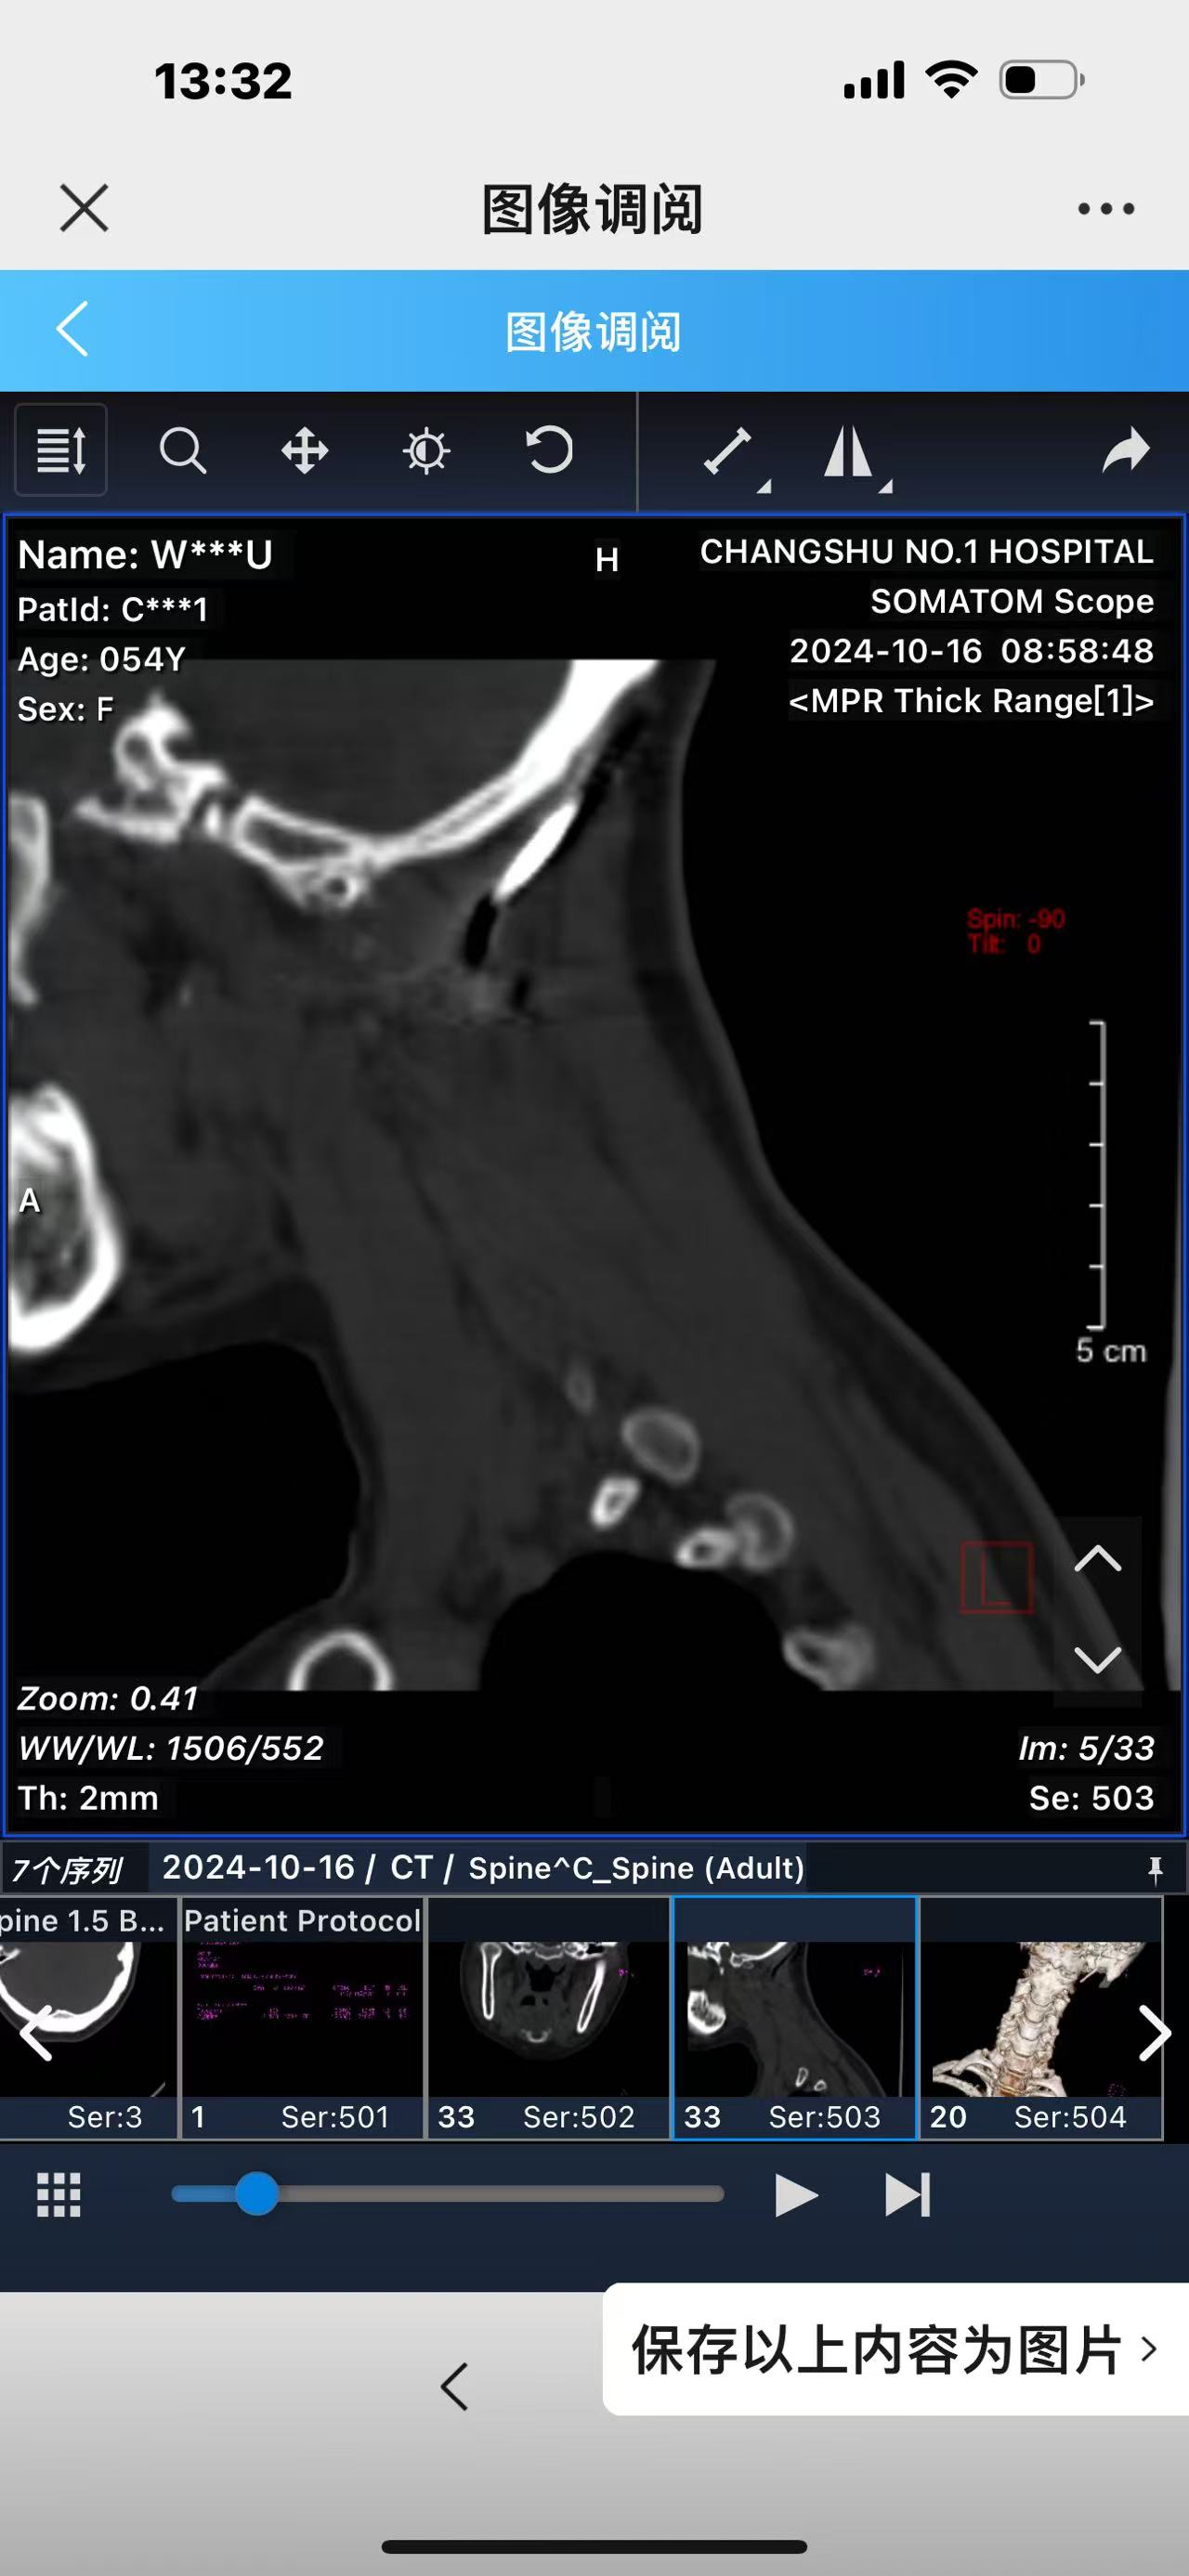

• 诊断:寰枢椎脱位,颅底凹陷

• 影像:

• 术后影像: